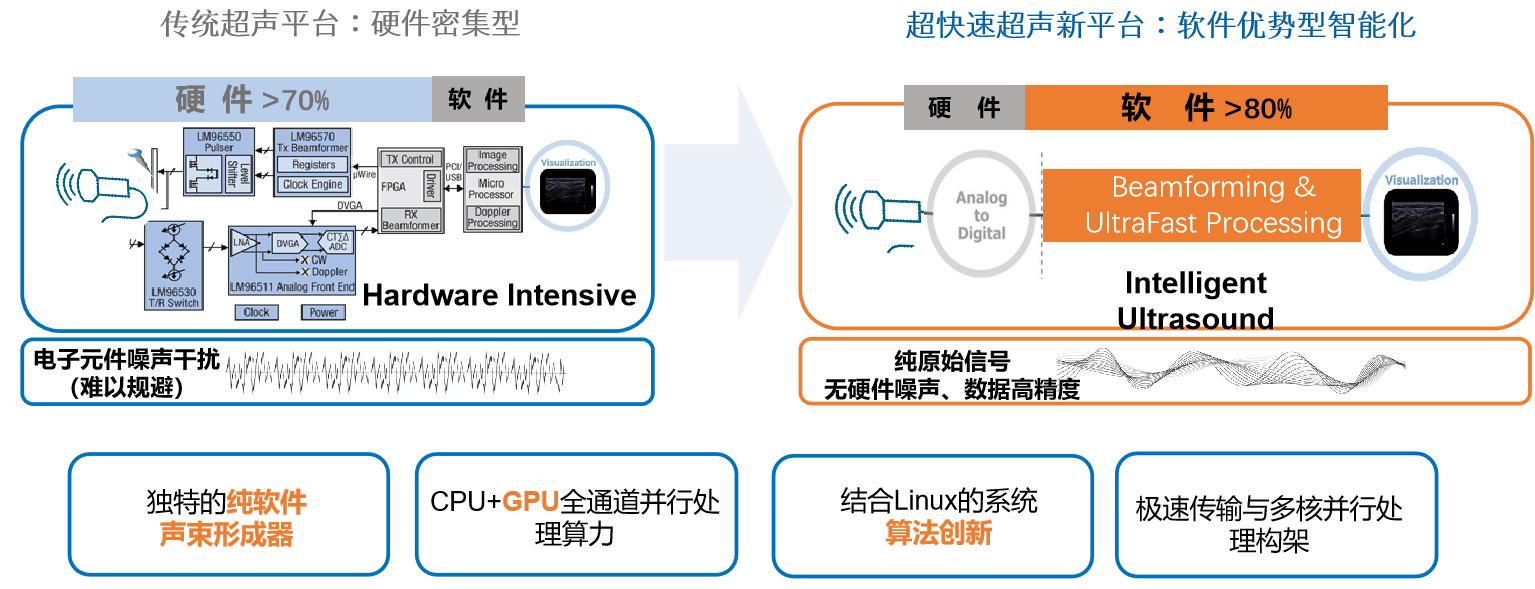

平面波超快速成像平台

硬件系统架构颠覆、创新软波束形成

优异的二维图像